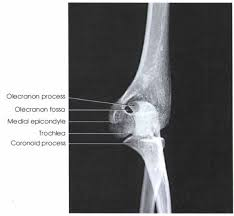

the ___ process on the proximal ukna articulates with the ___ of the distal hummerus when the elbow joint is in flexion.

coronoid process; coronoid fossa